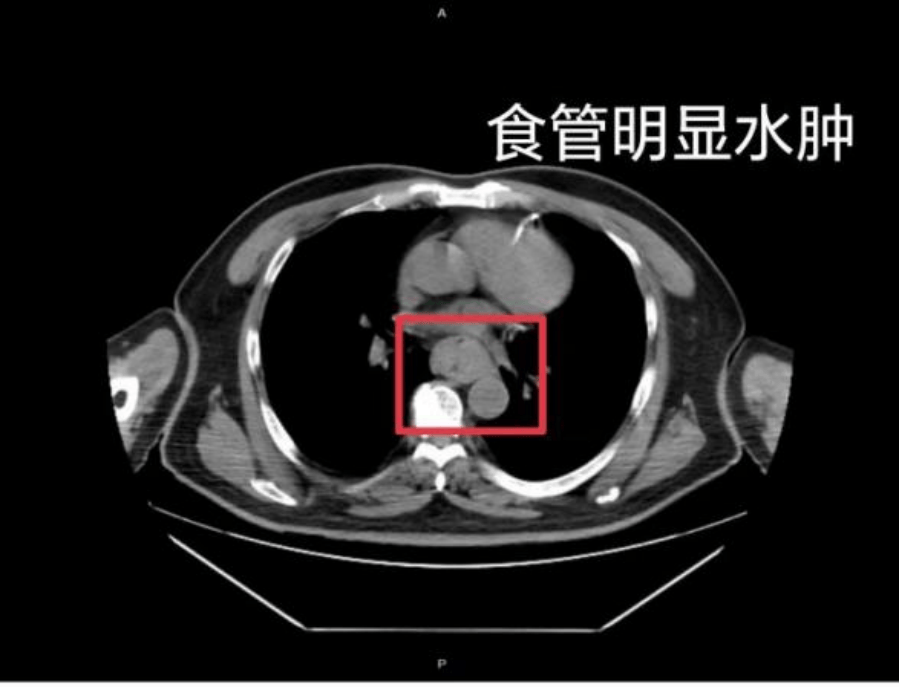

这样的情况并非个例,同样在近日,福州一位网友分享了自己因吃了一碗很烫的福鼎肉片导致呕血,并查出食管水肿的经历虚拟币钛币。

据网友回忆,“自己去厕所尝试呕吐时,直接呕出了血,一大口鲜血从嘴里喷出,总共吐了两次虚拟币钛币。”CT 结果显示,他的食管全部出现水肿损伤。